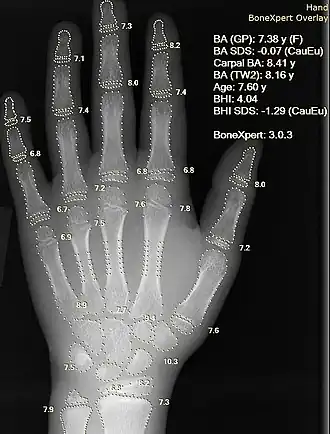

Image and sound processing

Information can take the form of images, sound, video or other multimedia. Bits of information can be streamed via signals. Its processing is the central notion of informatics, the European view on computing, which studies information processing algorithms independently of the type of information carrier – whether it is electrical, mechanical or biological. This field plays important role in information theory, telecommunications, information engineering and has applications in medical image computing and speech synthesis, among others. What is the lower bound on the complexity of fast Fourier transform algorithms? is one of the unsolved problems in theoretical computer science.

| FFT algorithms | Image processing | Speech recognition | Data compression | Medical image computing | Speech synthesis |